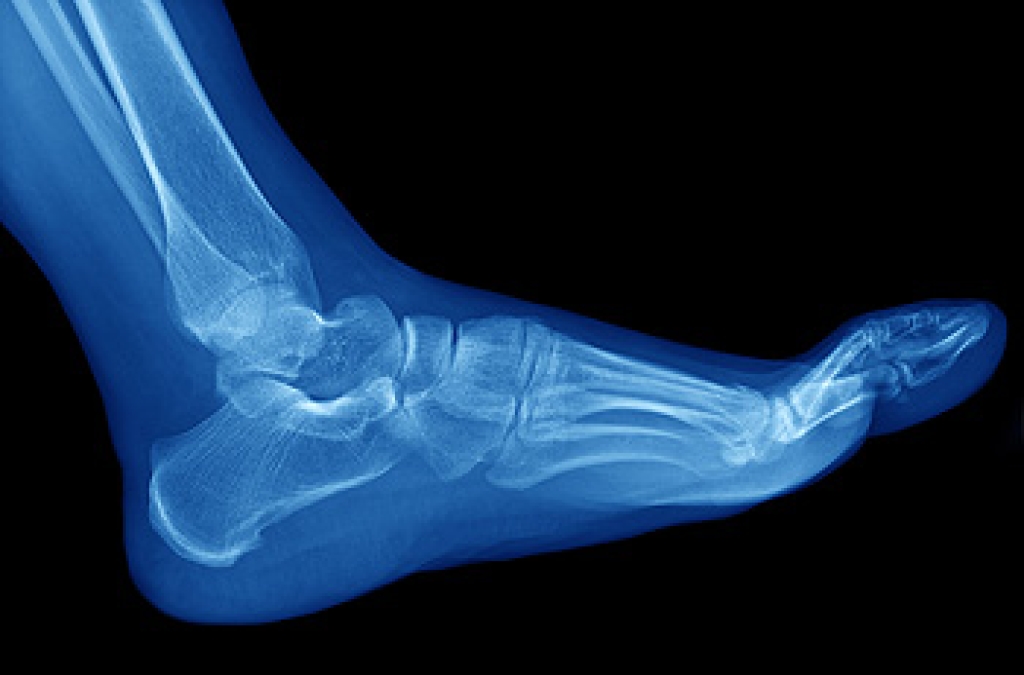

Due to the wide variety of potential causes of ankle pain, podiatrists will utilize a number of different methods to properly diagnose ankle pain. This can include asking for personal and family medical histories and of any recent injuries. Further diagnosis may include sensation tests, a physical examination, and potentially x-rays or other imaging tests.